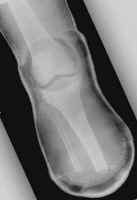

The images shown demonstrates a BKA of acceptable length. The patient is

wearing a prosthesis.